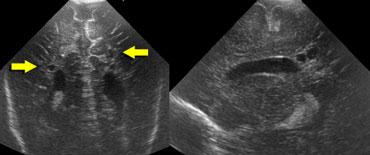

TRÁI: Hình ảnh khảo sát ban đầu cho thấy flaring. PHẢI: Hình ảnh tái khám sau một tuần cho thấy chất trắng quanh não thất bình thường.

Cần theo dõi tái khám để phân biệt flaring với PVL độ I.

Trường hợp bên trái minh họa một trẻ sinh non có hình ảnh flaring.

Tại lần tái khám, không ghi nhận sự hình thành nang và sau tuần đầu tiên, chất trắng quanh não thất trở về hình ảnh bình thường.